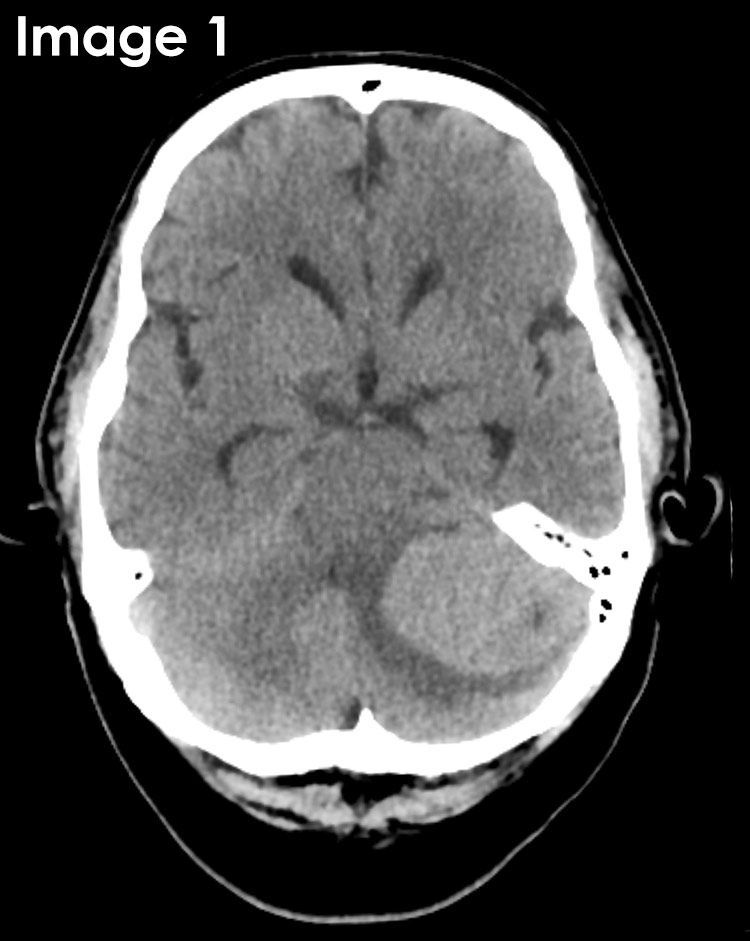

@RadMasterclass

Radiology Masterclass

6 months

CT BRAIN QUIZ: Pre + post-contrast: Postural headaches. Cerebellar signs. What is the most likely diagnosis? A: Subdural collection B: Subarachnoid haemorrhage C: Intraventricular haemorrhage D: Extradural haematoma E: Posterior fossa meningioma Start Quiz https://t.co/ATFl8YktNe

18

23

131